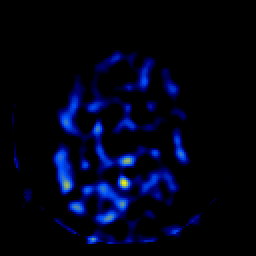

SPECT TL Study #6 -- Slice #47

[Home][Help][Clinical][Tour 1][Tour 2][Tour 3] Slice 47